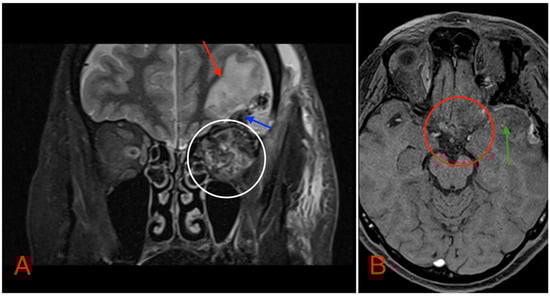

Postoperative head MRI showed partial resection of the left optic nerve. Residual tumor tissue and edema were noted in the left retrobulbar space, extending into the left prechiasmal space and into the left side of the optic chiasm (Figure 8).

Figure 8. (A) MRI image, T2 TSE STRI sequence, of the aftermath of the left-sided pterional craniotomy, showing postsurgical edema (red arrow) with a small hemorrhagic component (blue arrow). Postsurgical changes in the intraconal space can also be noted, showing an edema and a hemorrhage (white circle). (B) MRI image, T1 vibe post-gadolinium image sequence, showing postsurgical changes in the region of the optic chiasm with partial (subtotal) tumor resection (red circle). Local brain edema with hemorrhagic component (green arrow) can also be noted.